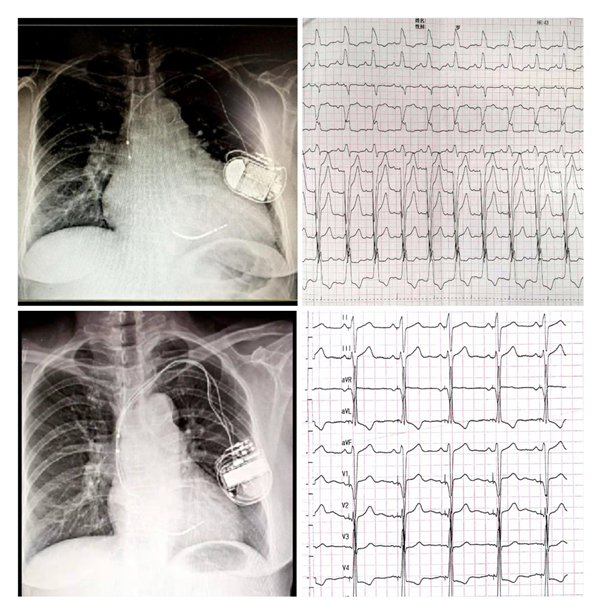

主播福利 为国内较早开展左束支起搏(LBBP)的中心之一,自2018年1月开展福建省首例LBBP以来,至今累计例数已近200例。中心采用黄伟剑教授的标准术式,手术成功率高、并发症少,随访导线参数稳定。此前起搏团队为1例外院CRT失败转诊主播福利 的患者实行左束支起搏治疗得到了良好的疗效,LVD从80mm 缩小至52mm,LVEF 从24%升高至60%,心脏完全恢复正常。目前厦心常规开展这一技术以造服更多的心衰患者。

(上图左上为CRTD术前,外院植入ICD2年,右上是自身完左心电图;左下为CRTD术后一年,右下为CRTD术后心电图)